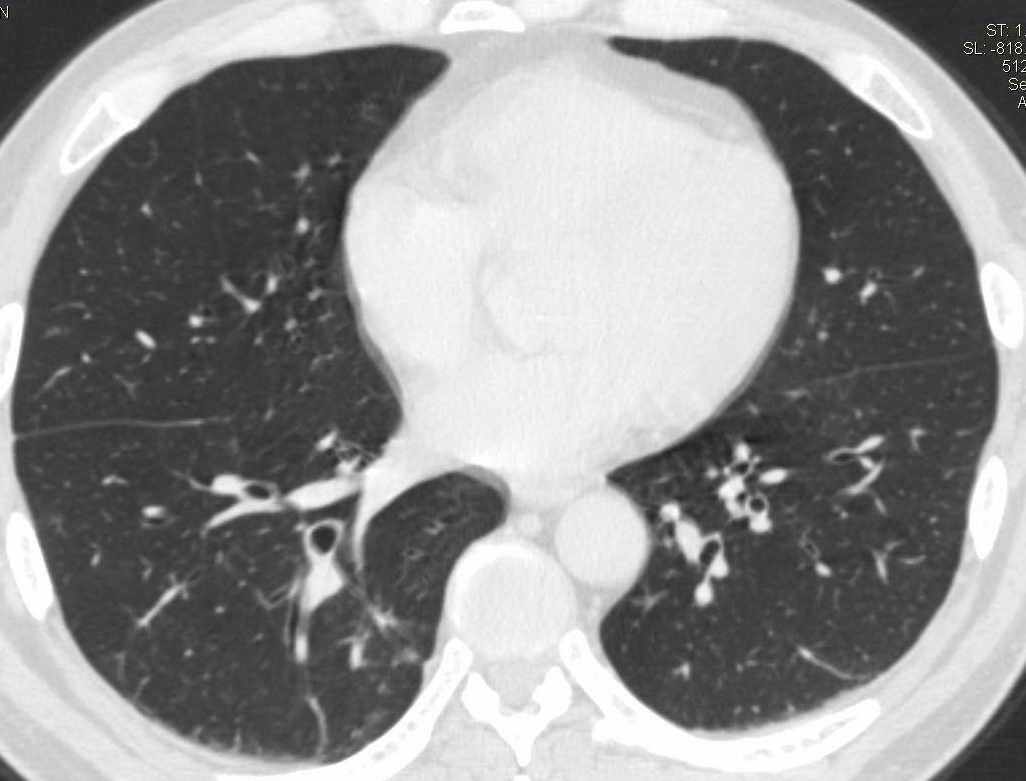

两肺下叶肺纹理增多、增粗并呈“树芽状”改变。支气管扩张呈囊状,部分呈柱状改变。其周围可见散在的斑片样及条索样密度增高影,右肺下叶近叶间胸膜可见一形态不规则的高密度结节影,并与胸膜粘连。

考虑:支扩并发感染。

双肺间质性改变(间质纤维化?)伴支扩。右肺下叶有毛刺的小结节,考虑周围型肺癌可能性。